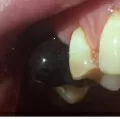

Добрый день! Двое суток назад удалила зуб (нижняя 6 слева). Удаление было сложным, искривление корней, зуб дробили и вынимали по частям, корни по одному. Лунка заполнилась сгустком, прикладывали холод, отека не было и нет. На второй день сгусток покрылся белым налетом, как и десна со стороны щеки. Но сегодня за ночь сгусток стал расти! Он как бы «подсобрался» в горку, все так же покрыт белым налетом и стал размером почти с зуб! Лунка при этом не болит, а поднывает и чешется! Кислый привкус во рту периодически! Нормально ли это? И какие предпринять действия?

Добрый день. Описанное вами состояние я является абсолютной нормой. Белый налет это фиброз, также норма. Расслабьтесь и выполняйте рекомендации доктора. Всего доброго.